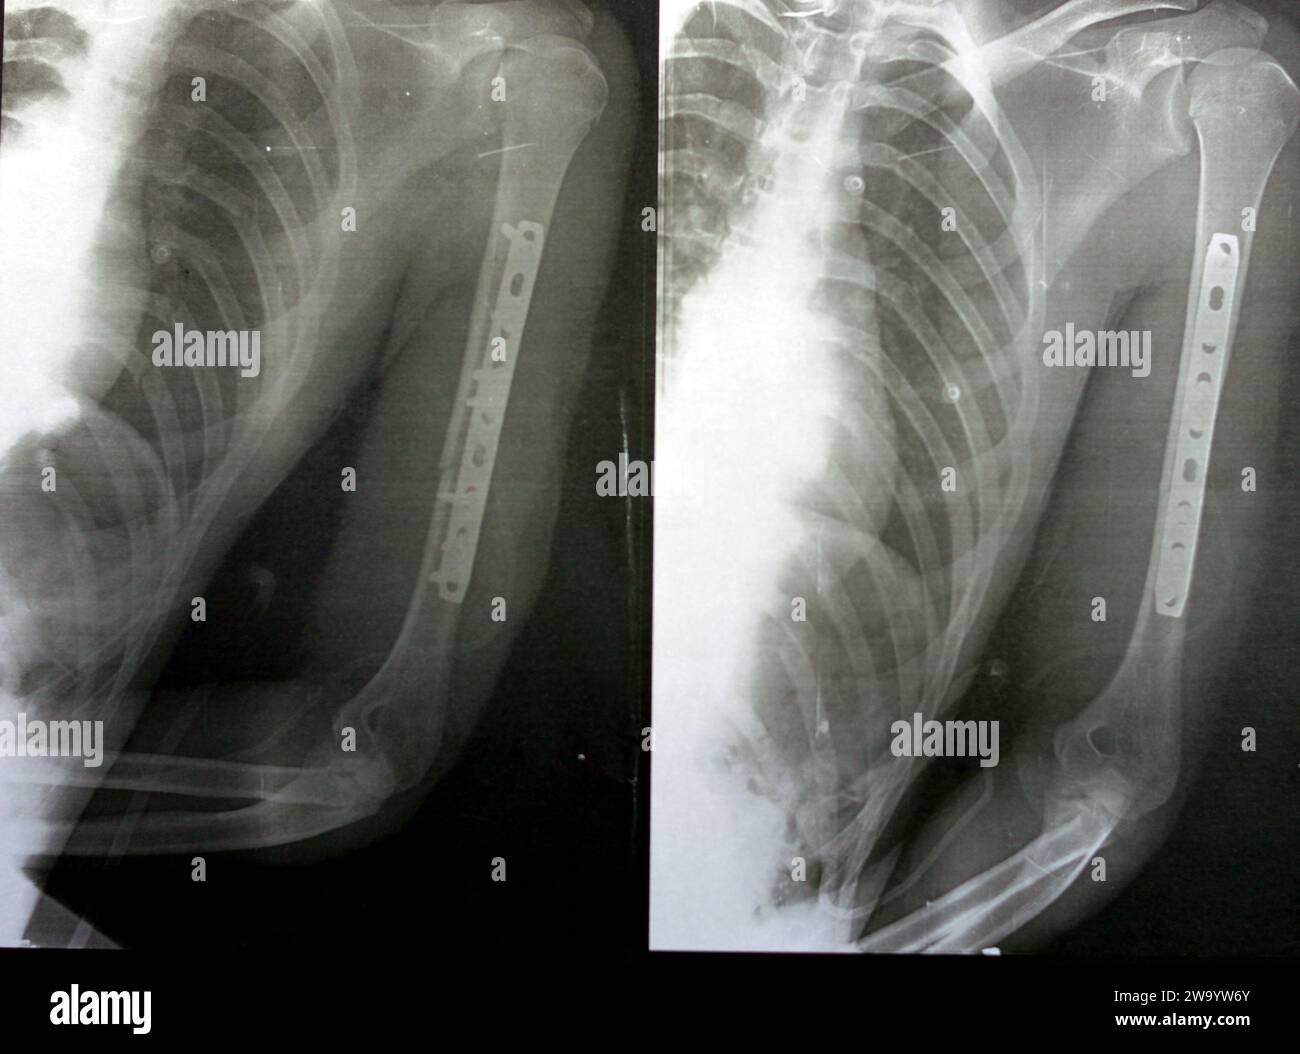

RF2WA30RC–Radiografia semplice che mostra frattura dell'omero sinistro dell'albero intermedio trasversale causata da un trauma diretto in un incidente stradale, gestito da riduzione aperta e fissa interna

RF2W9YW73–Radiografia semplice che mostra frattura dell'omero sinistro dell'albero intermedio trasversale causata da un trauma diretto in un incidente stradale, gestito da riduzione aperta e fissa interna

RF2WA2Y85–Radiografia semplice che mostra frattura dell'omero sinistro dell'albero intermedio trasversale causata da un trauma diretto in un incidente stradale, gestito da riduzione aperta e fissa interna

RF2W9YWMX–Radiografia semplice che mostra frattura dell'omero sinistro dell'albero intermedio trasversale causata da un trauma diretto in un incidente stradale, gestito da riduzione aperta e fissa interna

RF2W9YW6Y–Radiografia semplice che mostra frattura dell'omero sinistro dell'albero intermedio trasversale causata da un trauma diretto in un incidente stradale, gestito da riduzione aperta e fissa interna

RF2W9YWN6–Radiografia semplice che mostra frattura dell'omero sinistro dell'albero intermedio trasversale causata da un trauma diretto in un incidente stradale, gestito da riduzione aperta e fissa interna